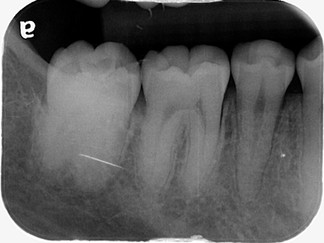

病患的右下第二大臼齒橫躺在骨頭裡面長不出來,背上又被智齒壓住啦

這樣的阻生齒,需要用矯正的方式拉出來,否則除了咬合的問題,

長久以來也常造成局部的牙周問題。